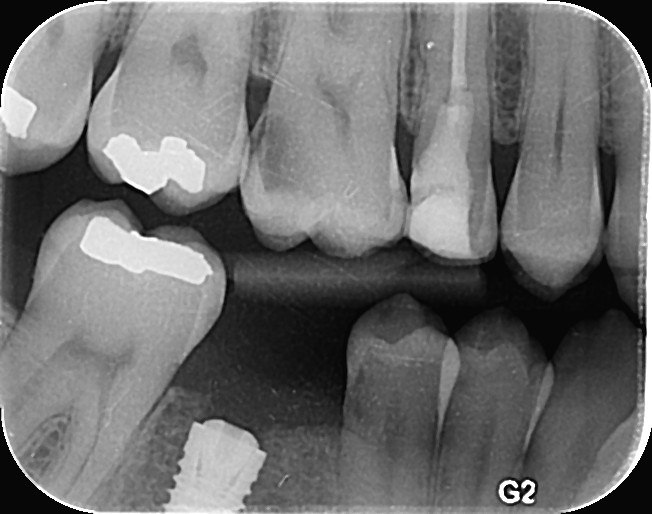

3. What is the caries level on the distal surface of the tooth # 3.6?

4. Which surface needs restoration?

5. Which surface needs restoration?

6: What is the caries level of mesial of the tooth # 3.6?

7: What is the caries level of Distal of the tooth # 3.6?

8. Which surface needs restoration?